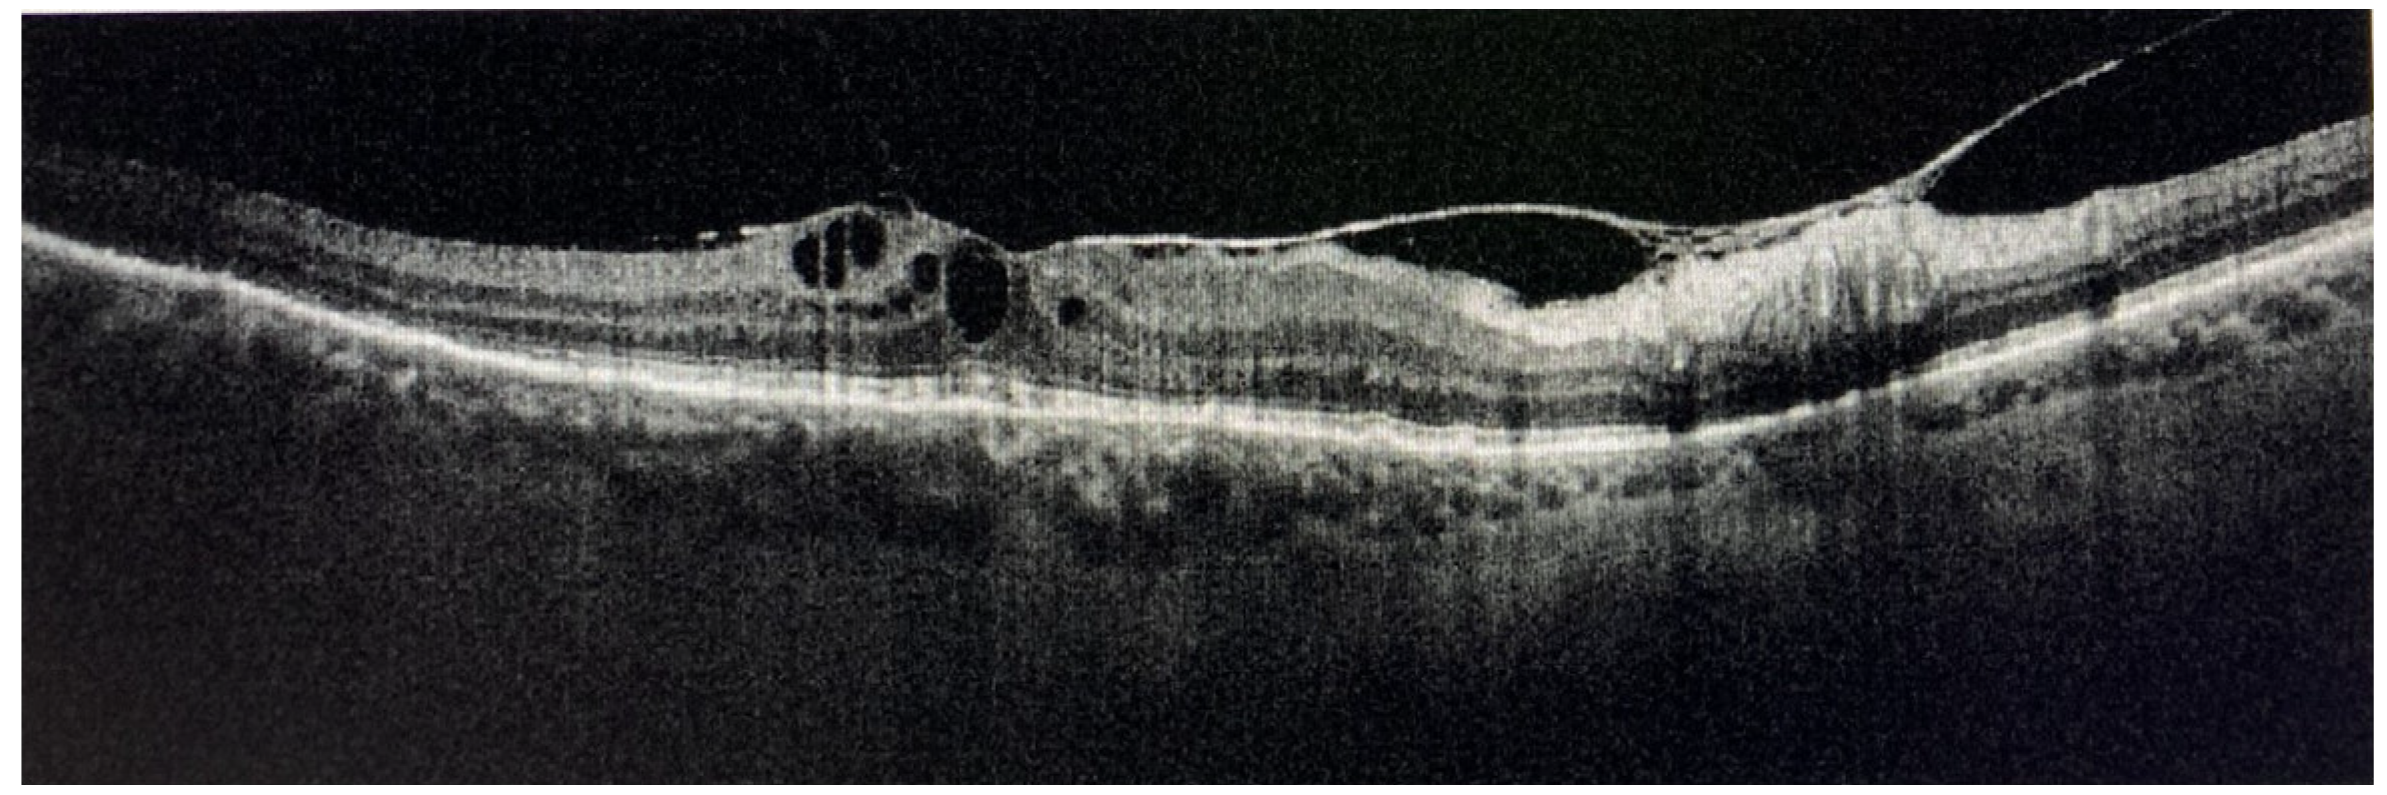

- Goldberg, N.R.; Jabs, D.A.; Busingye, J. Optical coherence tomography imaging of presumed sarcoid retinal and optic nerve nodules. Ocul. Immunol. Inflamm. 2016, 24, 293–296. [Google Scholar] [CrossRef] [PubMed]

- Invernizzi, A.; Agarwal, A.; Mapelli, C.; Ngyen, Q.D.; Staurenghi, G.; Viola, F. Longitudinal follow-up of choroidal granulomas using enhanced depth imaging optical coherence tomography. Retina 2017, 37, 144–153. [Google Scholar] [CrossRef] [PubMed]

- Pichi, F.; Sarraf, D.; Morara, M.; Mazumdar, S.; Neri, P.; Gupta, V. Pearls and pitfalls of optical coherence tomography angiography in the multimodal evaluation of uveitis. J. Ophthalmic Inflamm. Infect. 2017, 7, 20. [Google Scholar] [CrossRef]

- Mahendradas, P.; Madhu, S.; Kawali, A.; Govindaraj, I.; Gowda, P.B.; Vinekar, A.; Shetty, N.; Shetty, R.; Shetty, B.K. Combined depth imaging of choroid in uveitis. J. Ophthalmic Inflamm. Infect. 2014, 4, 18. [Google Scholar] [CrossRef][Green Version]

- Baltmr, A.; Lightman, S.; Tomkins-Netzer, O. Examining the Choroid in Ocular Inflammation: A Focus on Enhanced Depth Imaging. J. Ophthalmol. 2014, 2014, 459136. [Google Scholar] [CrossRef] [PubMed]

- Invernizzi, A.; Mapelli, C.; Viola, F.; Cigada, M.; Cimino, L.; Ratiglia, R.; Staurenghi, G.; Gupta, A. Choroidal granulomas visualized by enhanced depth imaging optical coherence tomography. Retina 2015, 35, 525–531. [Google Scholar] [CrossRef]

- Fardeau, C.; Champion, E.; Massamba, N.; LeHoang, P. Uveitic macular edema. Eye 2016, 30, 1277–1292. [Google Scholar] [CrossRef] [PubMed]

- Massa, H.; Pipis, S.Y.; Adewoyin, T.; Vergados, A.; Patra, S.; Panos, G.D. Macular edema associated with non-infectious uveitis: Pathophysiology, etiology, prevalence, impact and management challenges. Clin. Ophthalmol. 2019, 13, 1761–1777. [Google Scholar] [CrossRef] [PubMed]